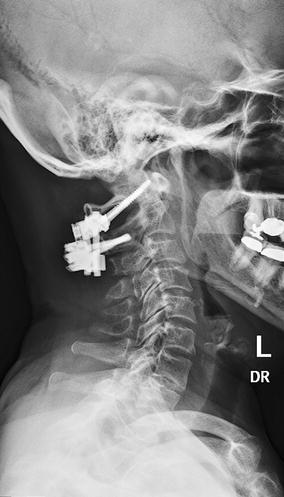

Laminal listhesis in 2021

Laminal listhesis picture This picture shows laminal listhesis.